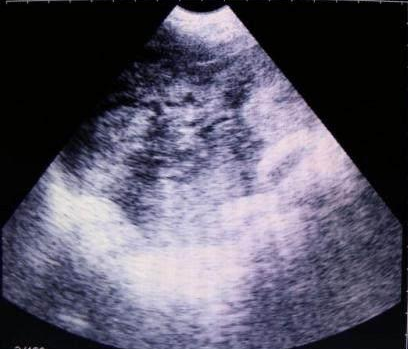

獸用B超機檢測母豬空懷圖像

需要注意的是,出現(xiàn)云團狀必須雙側(cè)檢查加以確認.根據(jù)B超機顯示圖我們大致可以判斷孕齡.圖像呈橢圓或者卵圓形大致為30天左右孕齡;圖像呈橢圓形或者卵圓形外,有明顯發(fā)亮骨骼圖像大致為50孕齡左右;圖像囊胚消失,發(fā)亮處隱約可見竹節(jié)狀東西為成型胎兒骨骼,一般為后期80孕齡以后。一般B超機成像會出現(xiàn)三種顏色,白色、黑色、灰色。白色為密度較高的物體,如骨骼或者結(jié)實.黑色一般為液體,包括血液、羊水、組織間隙液體、炎癥病灶等。灰色一般為實質(zhì)性物質(zhì),如肌肉。